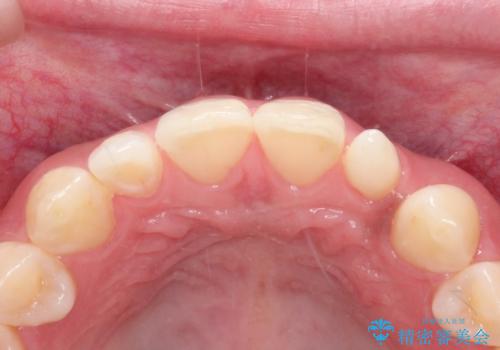

- 側切歯が小さいことを主訴に来院されました。

いくつかの治療の選択肢を説明し、オールセラミッククラウンで治療することとなりました。